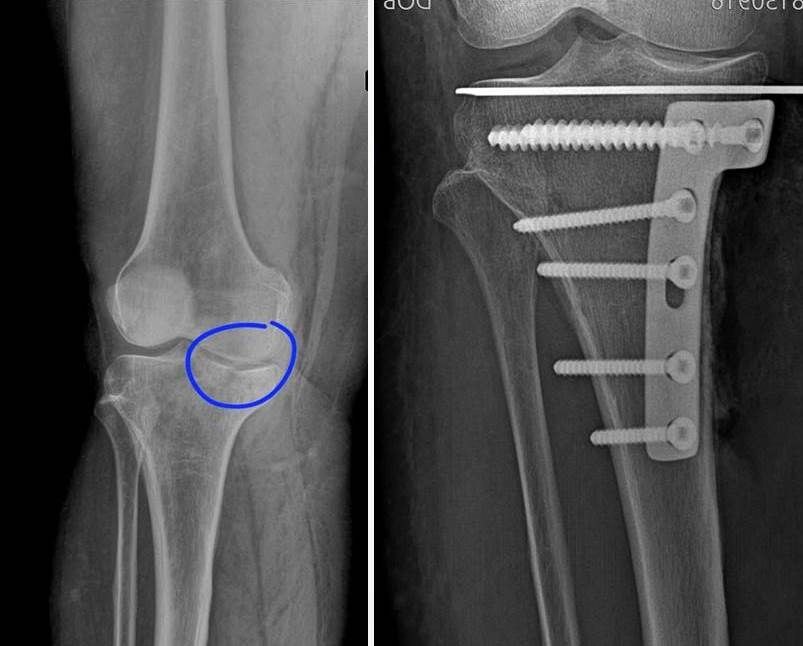

56-летнюю женщину доставили в городскую больницу №2 Воронежа с резкой болью в колене — она упала с лестницы. Обследование показало редкий и тяжёлый перелом: медиальный мыщелок большеберцовой кости был раздроблен, отломки сместились, в суставе — кровоизлияние.

Врачи приняли решение использовать в работе технологию, которую ранее в больнице не применяли. Вместо традиционного хирургического вмешательства они провели остеосинтез под контролем артроскопии — специальной камеры, вводимой в полость сустава через небольшой прокол.

Ход операции контролировался на экране. Без вскрытия сустава отломки сопоставили, зафиксировали спицей, а затем — титановой платиной и винтами. Всё — через минимальный доступ.